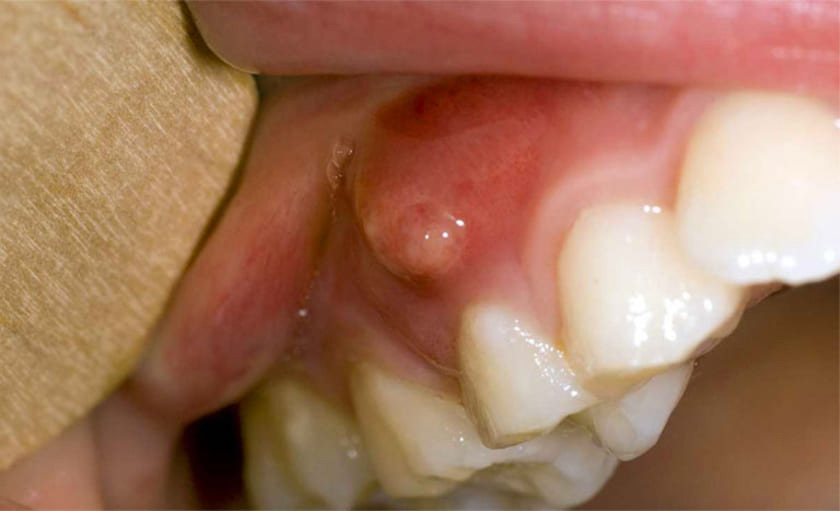

Áp xe răng

Áp xe răng có thể xảy ra ở chân răng (quanh chóp răng) hoặc ở mặt bên của chân răng (nha chu). Áp xe chứa đầy mủ và thường do sâu răng, chấn thương hoặc thủ thuật thẩm mỹ gây ra các vấn đề răng miệng (quá trình thẩm mỹ tạo vết nứt khiến cho vi khuẩn xâm nhập làm răng bị nhiễm trùng).

Các triệu chứng của áp xe răng bao gồm:

- Đau nhói răng

- Sưng hạch bạch huyết ở hàm hoặc cổ

- Sốt

- Nhạy cảm với nhiệt độ nóng và lạnh

- Sưng mặt và cổ

- Ê buốt khi cắn hoặc nhai